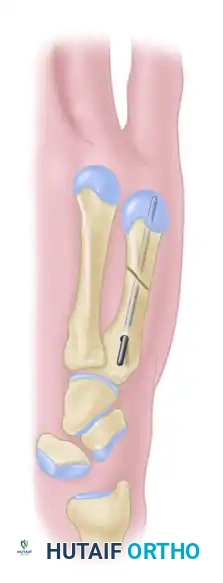

FIGURE 67-36A: Diagram illustrating an irreducible metacarpal shaft fracture requiring open reduction.

FIGURE 67-36B: Introduction of the intramedullary wire through the proximal fragment.

FIGURE 67-36C: Direct open reduction of the fracture fragments.

FIGURE 67-36D: Final seating of the intramedullary wire across the reduced fracture site.